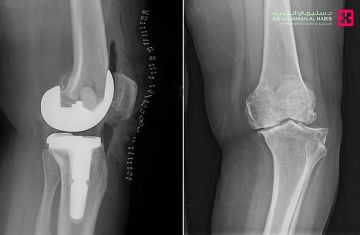

نجح مستشفى الدكتور سليمان الحبيب بالقصيم في إجراء عملية نوعية ناجحة لاستبدال مفصل الركبة اليسرى بتقنية حديثة تُخفّف الآلام وتُسرّع التعافي، منهيةً معاناة سيدة ستينية كانت تعاني من خشونة شديدة واحتكاك حاد وتلف في غضاريف المفصل.

وأوضح الدكتور عبدالله الشهراني، استشاري جراحة العظام واستبدال المفاصل الصناعية ورئيس الفريق الطبي المعالج، أن المريضة حضرت وهي تشكو من آلام وتورم وتغيّر في شكل الركبة وصعوبة في الحركة. وأضاف أن الفحص السريري والفحوصات الدقيقة أظهرت وجود احتكاك حاد وتآكل في عظمتي المفصل، إضافة إلى ارتخاء شديد في الأربطة الجانبية وخلل في حركة عظمة رأس الركبة.

وبيّن الشهراني أن الفريق الطبي درس الحالة بدقة، وتوصّل إلى أن استبدال المفصل بآخر صناعي هو الخيار الأنسب، حيث أُجريت العملية باستخدام مفصل خاص بهذه الحالات وبالاستعانة بأحدث الأجهزة الطبية. واستغرقت العملية نحو 60 دقيقة، وتكللت بالنجاح، إذ تمكّنت المريضة من المشي بعد ساعات فقط من إجرائها، وغادرت المستشفى بعد أيام بحالة صحية جيدة.

وأشار الشهراني إلى أن التقنية المستخدمة تختلف عن الطرق التقليدية، إذ لا تتطلب قطع رباط العضلة الرباعية وتحافظ على الأنسجة المحيطة، مما يقلل الآلام بعد الجراحة ويُسهم في تقصير فترات التنويم والعلاج الطبيعي والتأهيل.